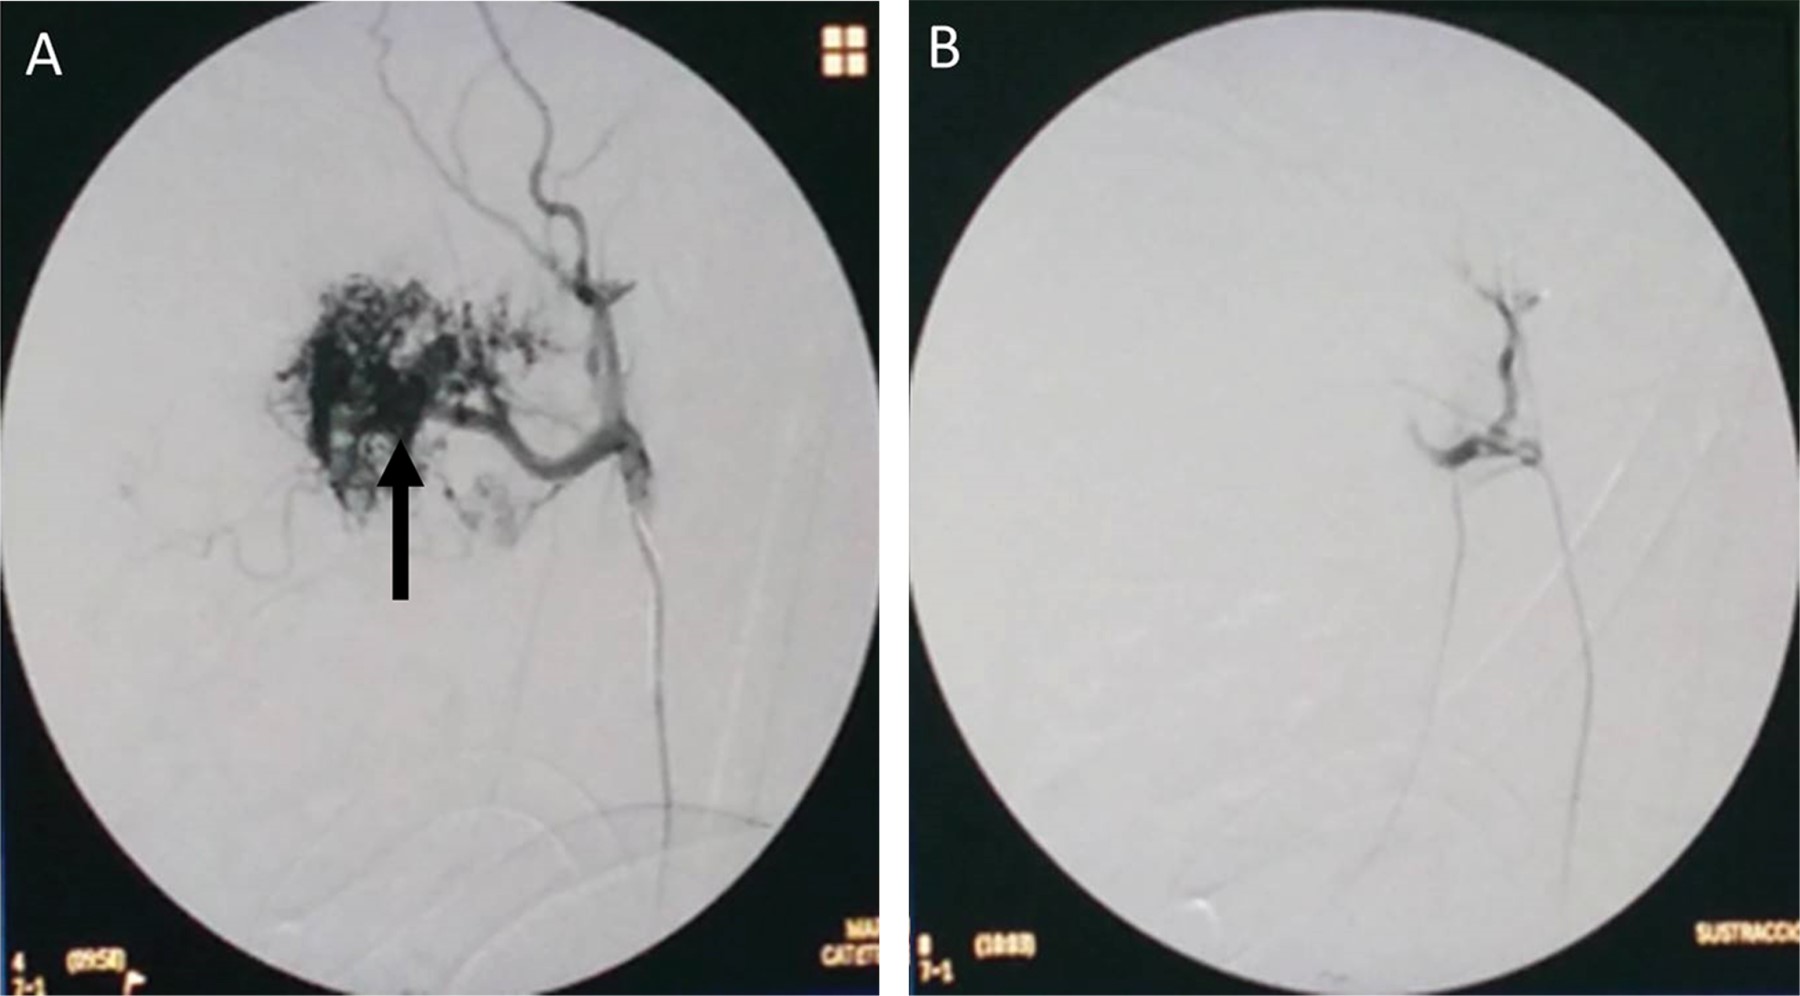

Introduction: juvenile nasopharyngeal angiofibroma is a benign tumor but can cause morbidity and mortality. We present a pediatric patient who had a successful resolution by surgical resection. Clinical case: ten-year-old male, with a history of nine months of unilateral nasal obstruction of approximately, associated with episodes of rhinorrhea, nocturnal hoarseness, mouth breathing, hyposmia and recurrent epistaxis. Imaging studies identified a tumor with irregular borders at the paranasal sinuses, concluding that it was a nasopharyngeal angiofibroma in stage IIb of the Radkowski classification. Tumor embolization is performed, and after 24 hours the tumor is removed by nasal endoscopic surgery. One year after resection, no tumor recurrence was documented. Conclusion: patients with juvenile nasopharyngeal angiofibroma are usually male, in the second decade of life, and with epistaxis as the main manifestation. Its treatment is surgical, with infrequent recurrences.

Figure 1